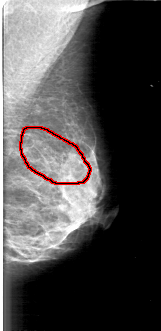

D_4168_1.LEFT_MLO

FILE: D_4168_1.LEFT_MLO.OVERLAY

TOTAL_ABNORMALITIES 1

ABNORMALITY 1

LESION_TYPE CALCIFICATION TYPE AMORPHOUS DISTRIBUTION SEGMENTAL

ASSESSMENT 0

SUBTLETY 4

PATHOLOGY BENIGN

TOTAL_OUTLINES 1

BOUNDARY